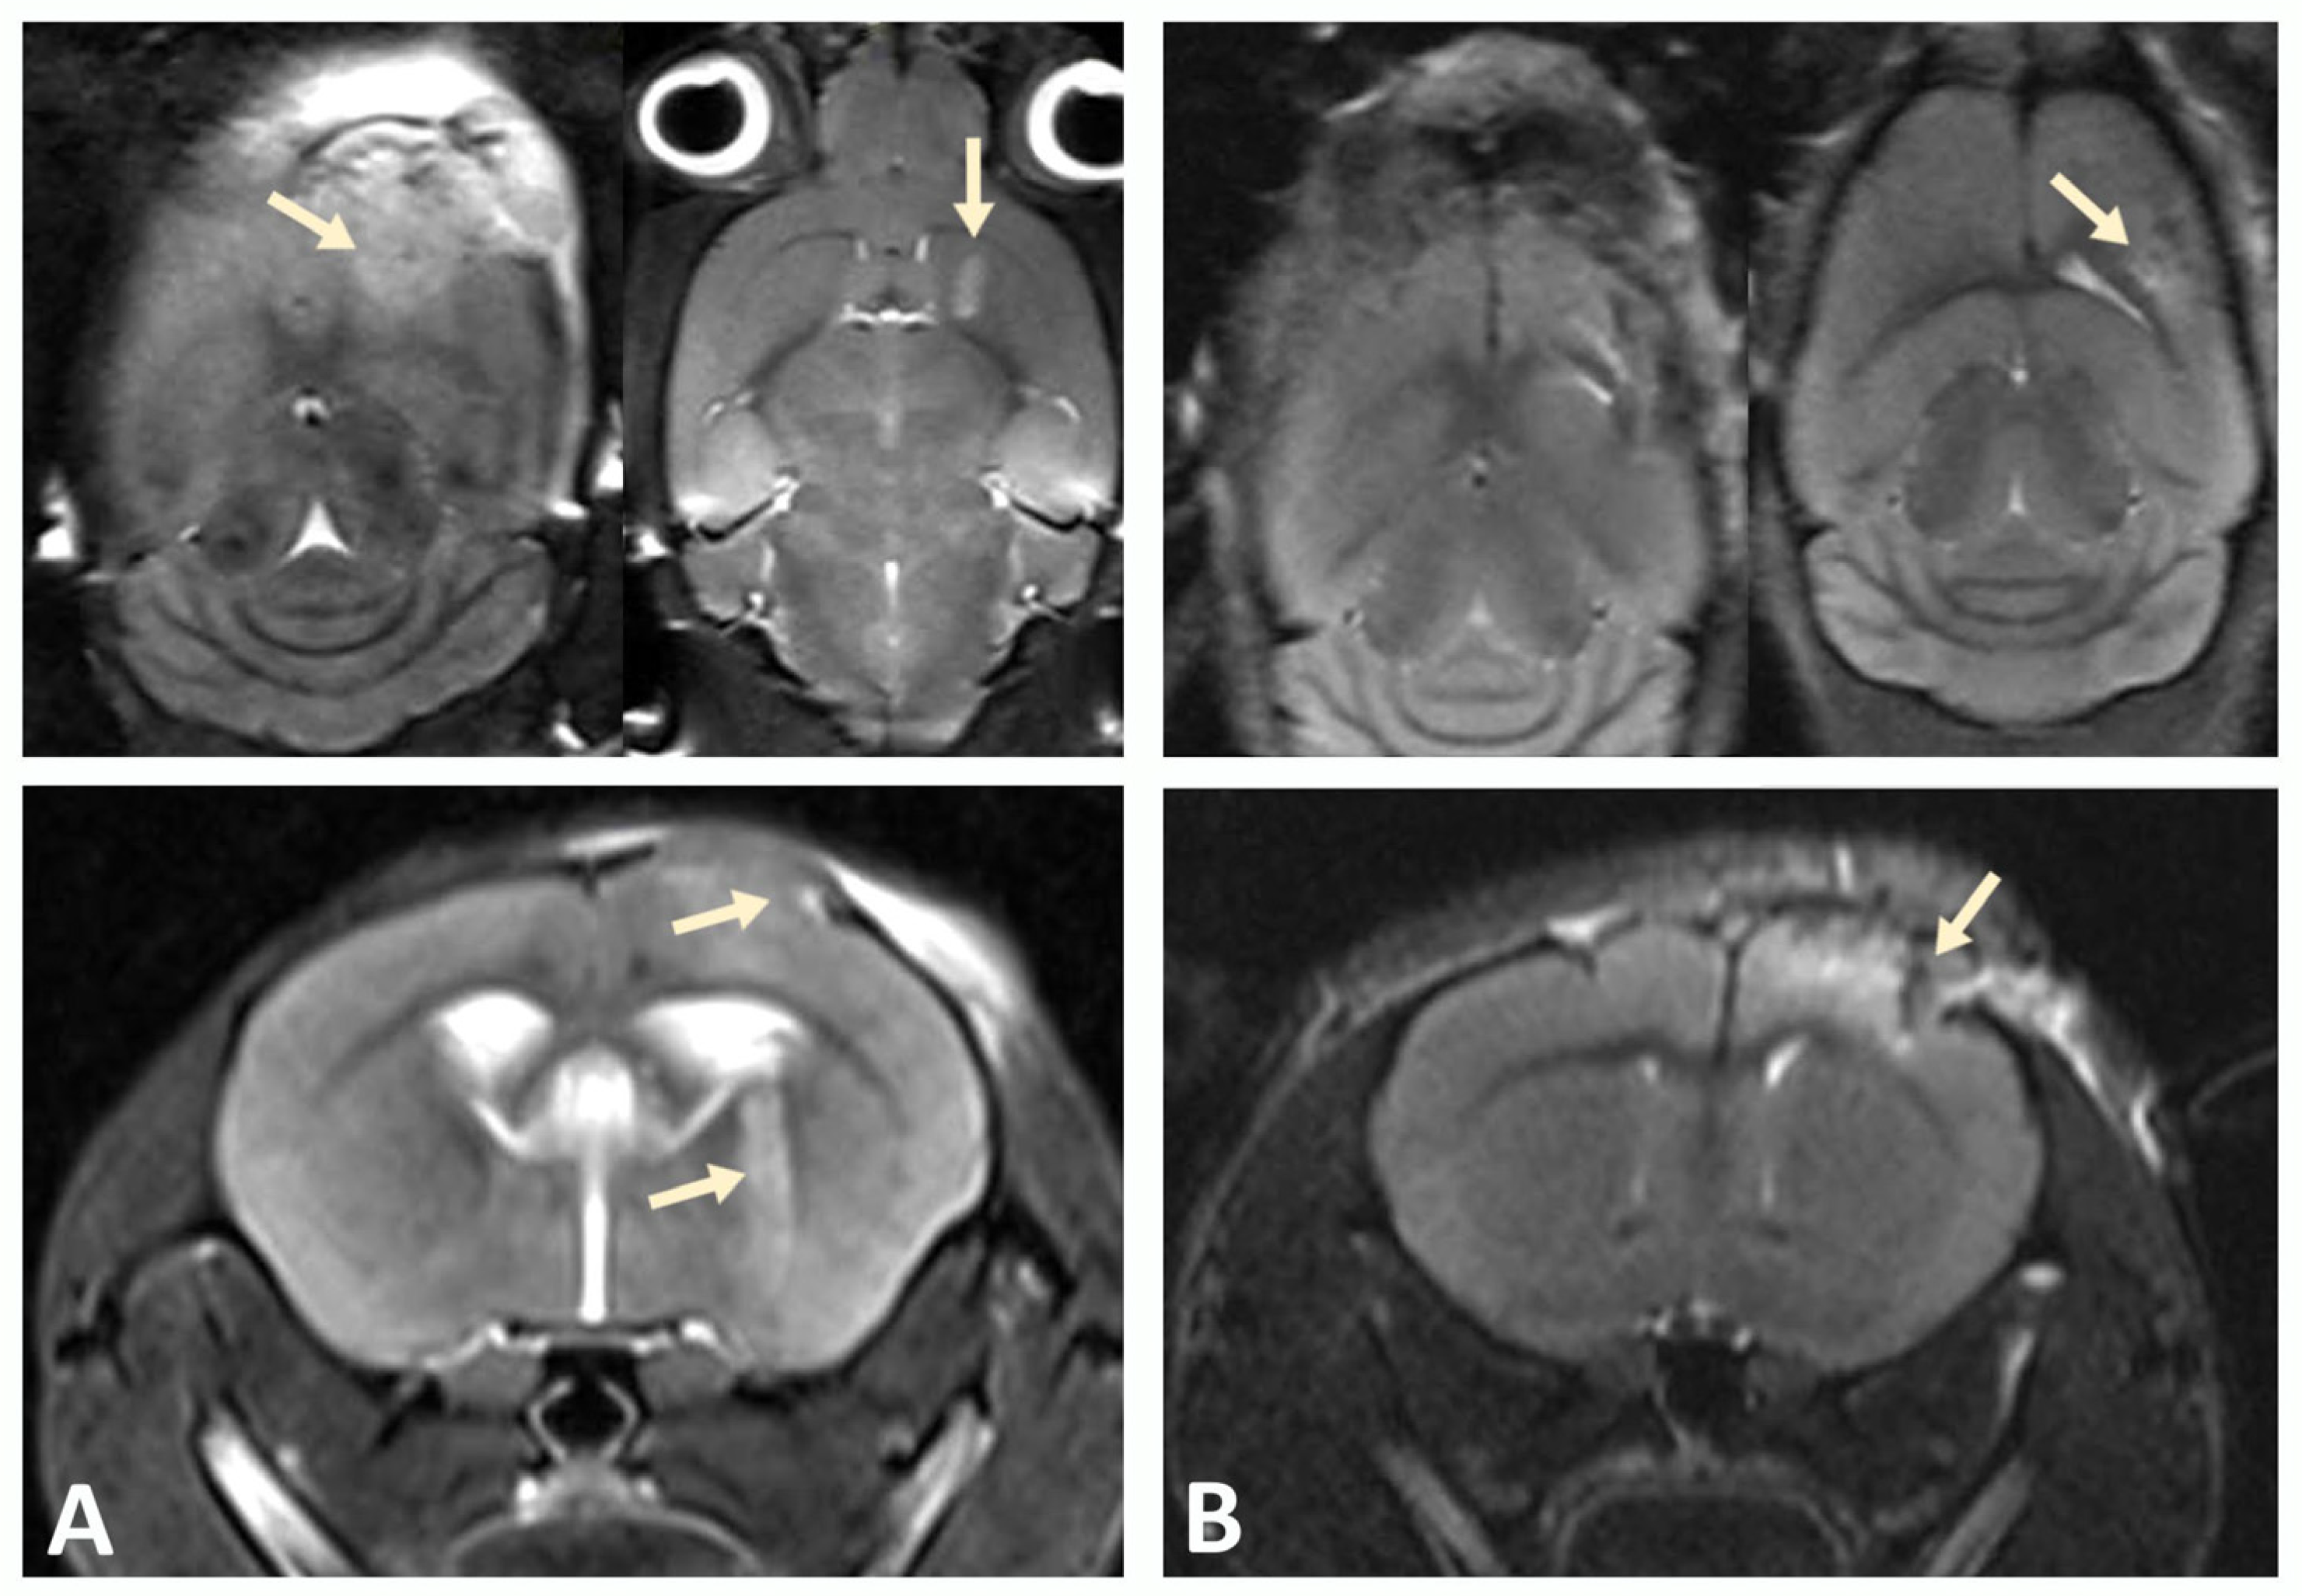

3.2. MRI Confirms Successful Engraftment of Human GBM PDX Cells in the Brain of NSG Mice

A xenograft model was developed by stereotactic implantation of a suspension of glioblastoma (GBM) cells into the striatum of the right hemisphere of immunodeficient NSG mice. The MRI was used to assess tumor growth at the injection site and GBM cell migration after implantation in a mouse brain to validate successful establishment of the xenograft model. Scanning was performed in three projections to determine the direction of tumor cell migration within the mouse brain tissue. Tumor growth was observed in the injection zone, which confirmed the successful engraftment of human GBM xenograft cells and corresponded to the expected parameters of the model (Figure 3).